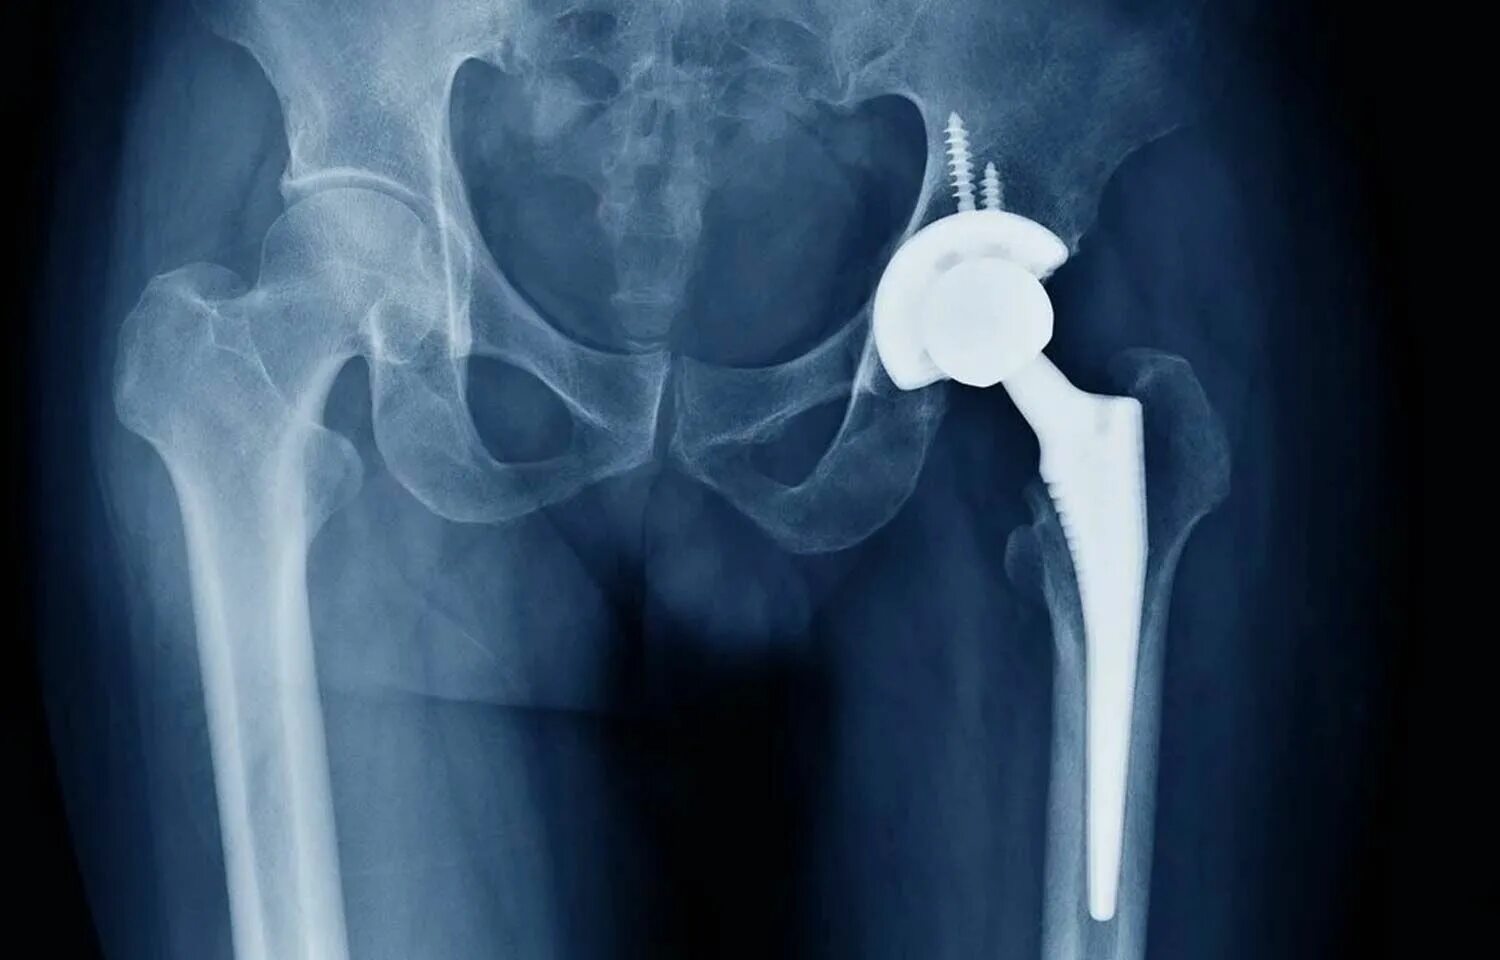

Эндопротез тазобедренного сустава москве